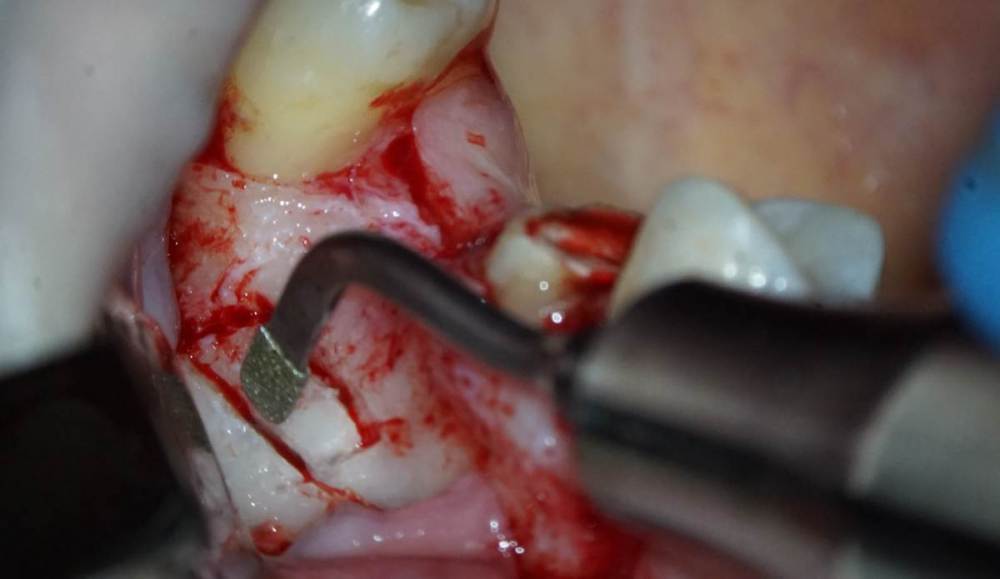

TIGER Опубликовано 8 мая, 2023 Автор Поделиться Опубликовано 8 мая, 2023 Всем привет!планировал удаление,но во время синуса решил использовать фрагмент как клин для стабилизации болта,в итоге совершил ошибку с более медиальной позицией 26,ибо шаблон не изготовил....через 5 мес одел времяхи,т.к будет тотал Ссылка на комментарий